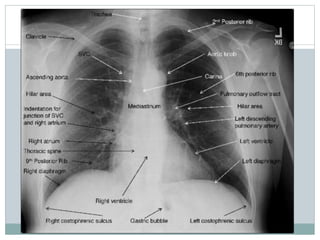

ANATOMIA RADIÓLOGICA

Avaliação Do Mediastino

 Mediastino

Superior

Inferior

 Traqueia

 Bronquios

 Angulos

Costofrenicos/

cardio

 Pulmões

Costelas

POST ANT

Diafragma